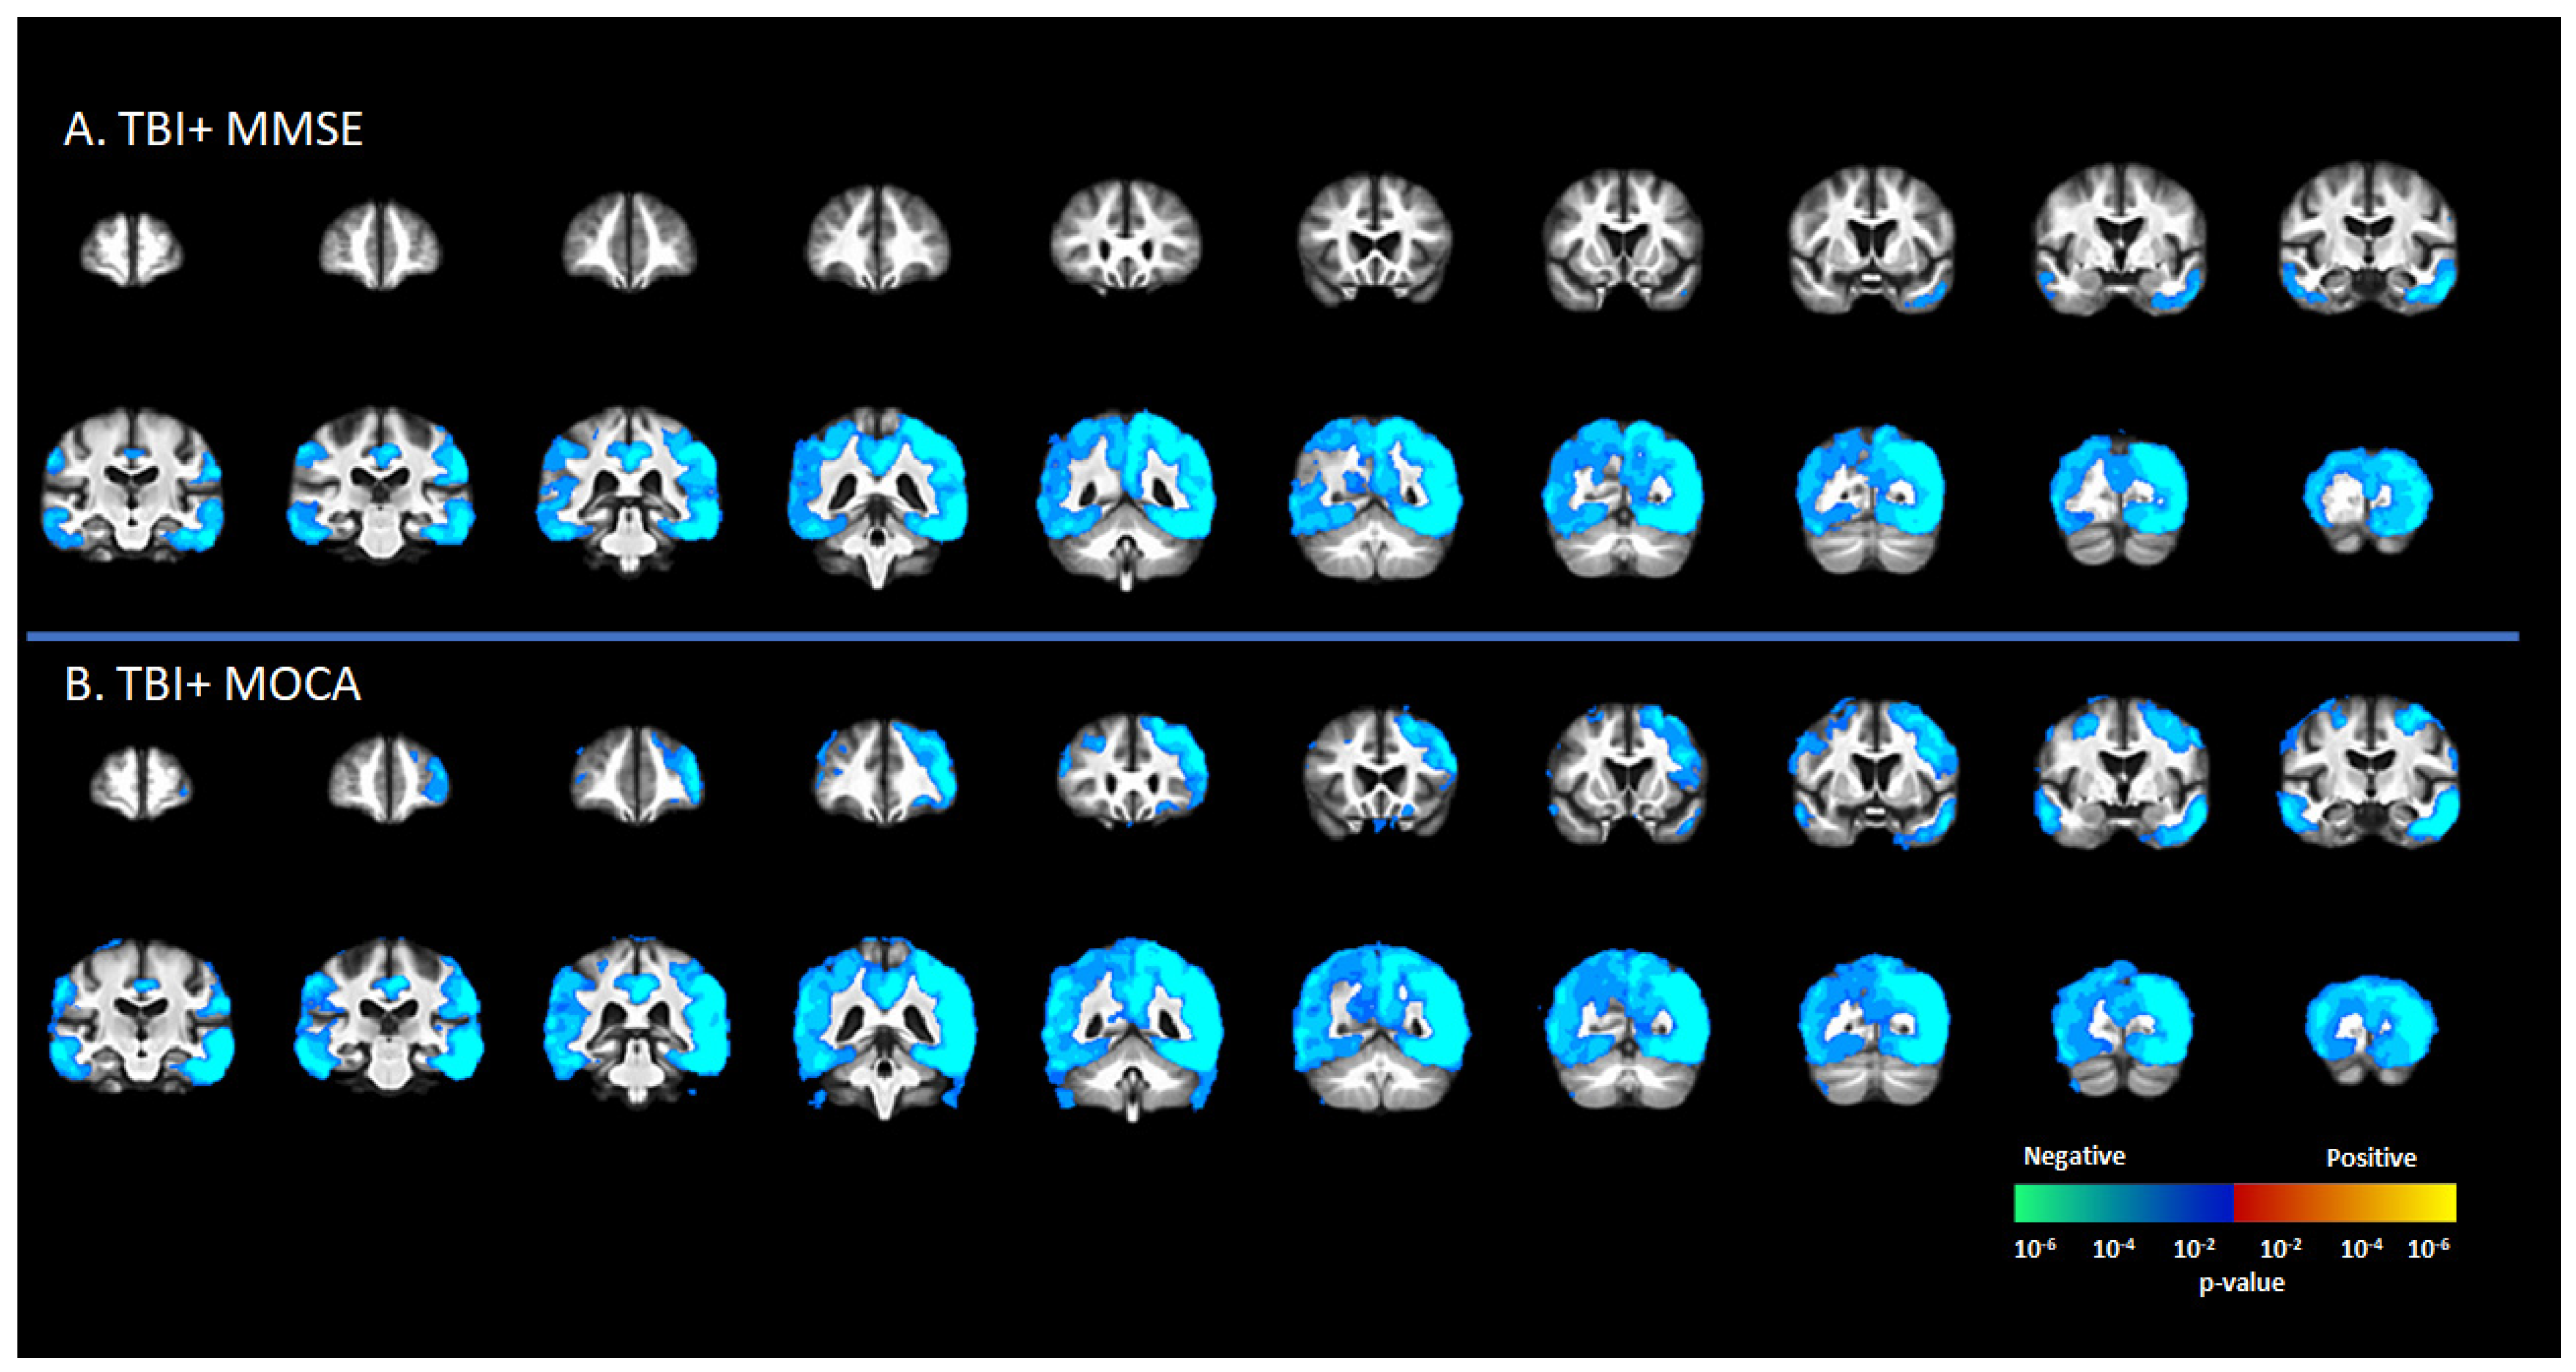

There was a significant negative correlation between tau deposition to [18F]-AV1451 SUVr and MMSE score in the TBI+ group (including CDR = 0 and CDR ≥ 0.5 subgroups) in areas such as the SFG, MFG, IFG, hippocampus, transentorhinal cortex, inferior temporal gyrus, middle temporal gyrus, superior temporal gyrus, temporal pole, lingual gyrus, fusiform gyrus, angular gyrus, insula, superior parietal gyrus, inferior parietal gyrus, PCC, ACC, and precunus (p < 0.05, Figure 3A). These same regions showed negative correlations between [18F]-AV1451 SUVr and MOCA scores (p < 0.05, Figure 3B).

Figure 3. Correlation between [18F]-AV1451 SUVr maps and different cognitive test scores in the elderly population with a self-reported history of traumatic brain injury (TBI), with results showing negative correlations between tau deposition and (A) mini-mental state scale (MMSE) and (B) Montreal cognitive assessment (MOCA). Red-yellow represents a positive correlation between tau accumulation in people with self-reported history of TBI and cognitive scores, while blue-green represents negative correlation between tau accumulation and cognitive scores.